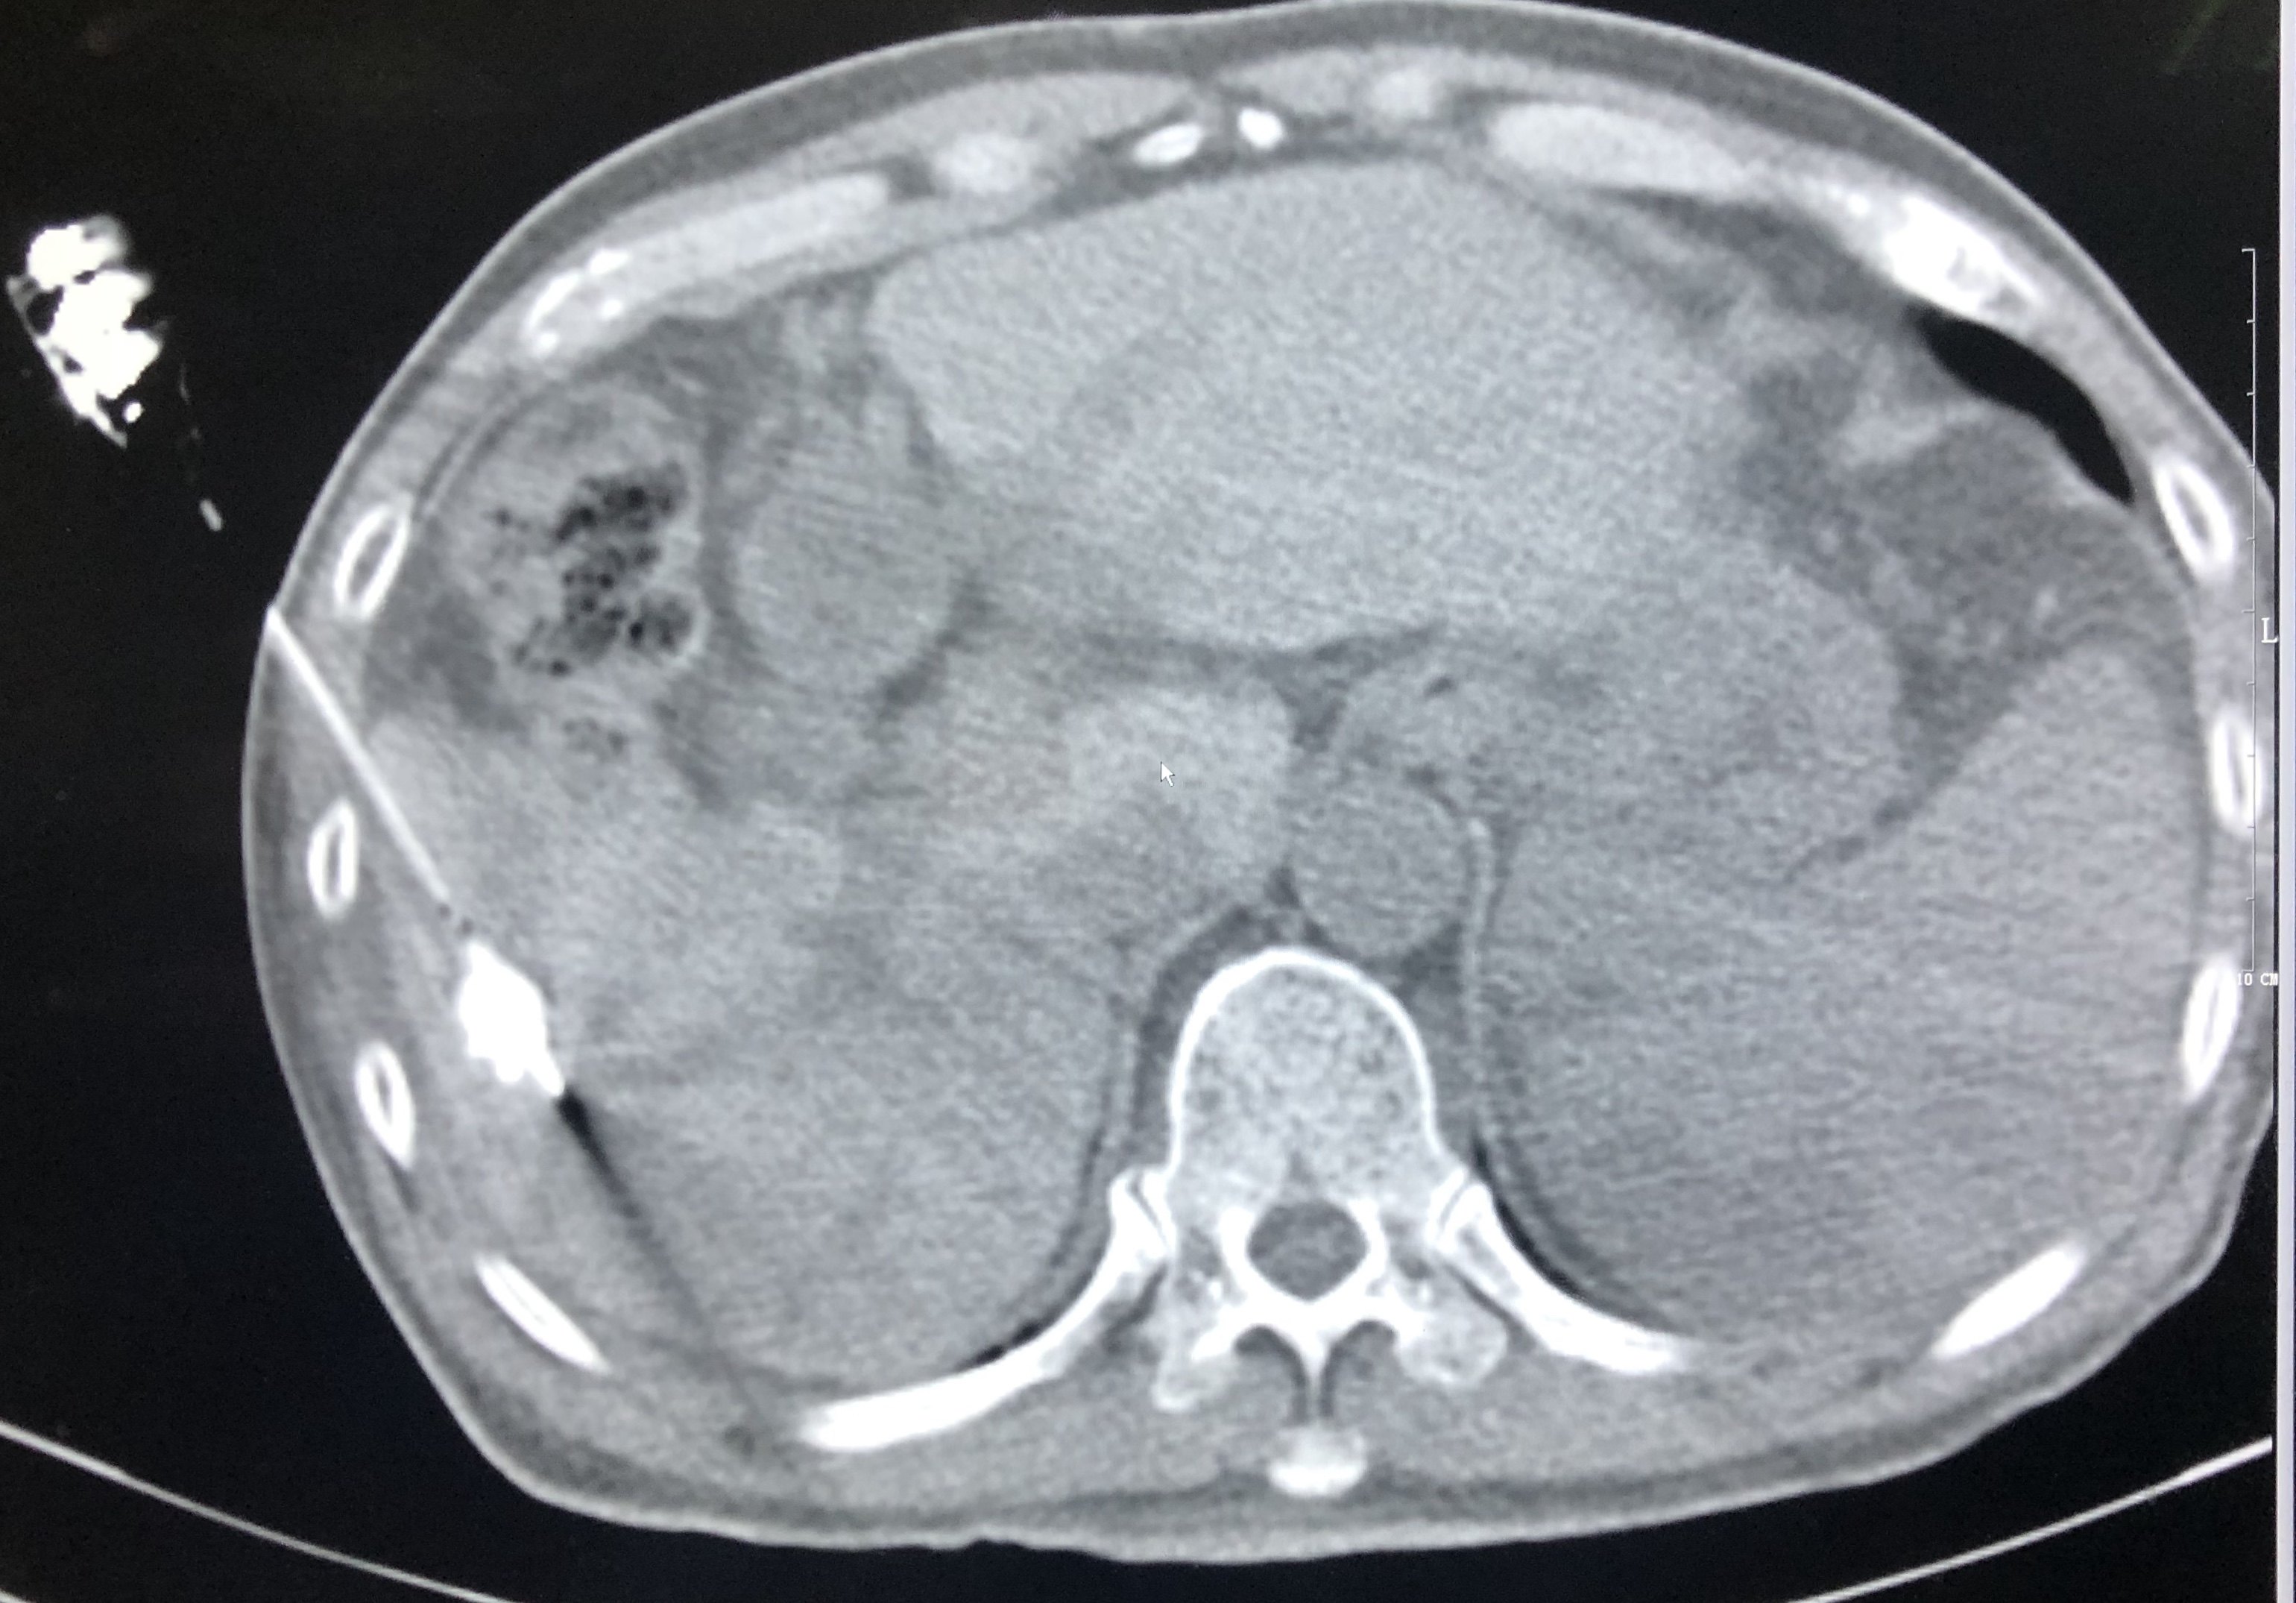

行脾脏多点消融治疗,以15g微波消融针穿刺脾脏,并进行大功率多位点消融治疗。

行脾脏多点消融治疗,以15g微波消融针穿

刺脾脏,并进行大功率多位点消融治疗。